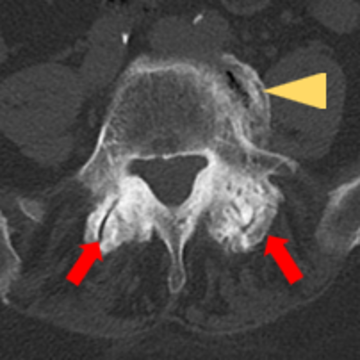

Ein CT-Horizontalschnitt zeigt, dass die kleinen Wirbelgelenke durch Arthrose in ihrer Beweglichkeit eingeschränkt und der Gelenkspalt reduziert sein kann (rote Pfeile). Zusätzlich können Knochenbrücken zwischen benachbarten Wirbelkörpern (gelber Pfeil) entstehen, was zu einer weiteren Belastung der Wirbelsäule führt.

Auf dem Bild ist ein CT-Horizontalschnitt durch einen Wirbelkörper zu sehen. Der rote Pfeil zeigt kleine Wirbelkörpergelenke mit Verlust der Beweglichkeit und Aufbrauchen des Gelenkspalts durch Arthrose. Der gelbe Pfeil zeigt benachbarte wirbelkörperüberspannende Knochenbrücken.